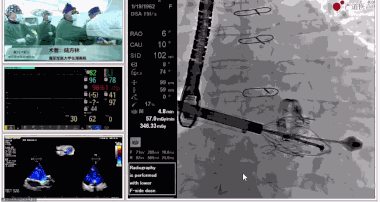

▲瓣膜植入后釋放的過程

▲瓣膜植入后三維超聲影像

▲瓣膜植入后右心室造影

在手術(shù)直播中瓣膜植入過程不到10分鐘,手術(shù)獲得圓滿成功,充分體現(xiàn)徐志云、陸方林團(tuán)隊(duì)技術(shù)精湛,團(tuán)隊(duì)協(xié)作默契及器械的優(yōu)越性。